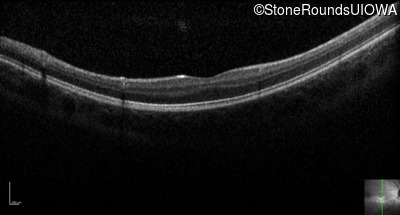

Optical Coherence Tomography - Left - 20/80 -2

Exemplar / OCT Stack

OCT Stack